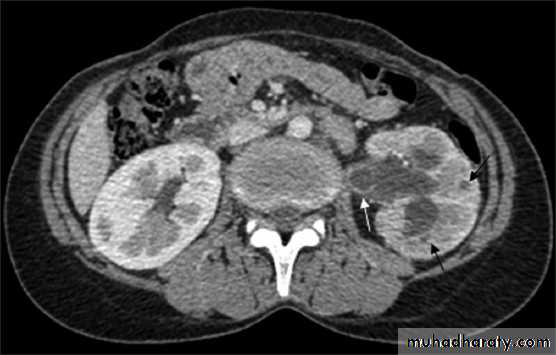

Computed Tomography

CT